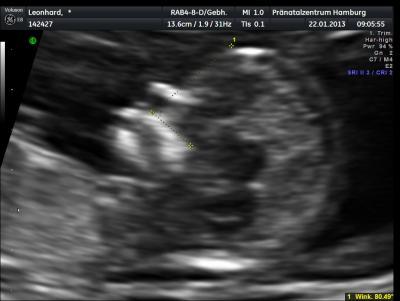

Hallo ihr lieben, es war so schön und die Werte sind top. Unser Krümel war leider nicht so vorbildlich,hat sich sehr viel bewegt und die Ärztin hatte zu tun ein gutes Bild zu bekommen! Wir haben einen ganzen USB-Stick voll mit Bildern bekommen!!!! Habe euch ein BIld mit angehängt! BIn heute 12+3. Liebe Grüße Dörte

Bild zu Bericht der Nackenfaltenmessung - Forum für August - Mamis

Das freut mich sehr! Und ein richtig tolles Bild hast du gepostet...